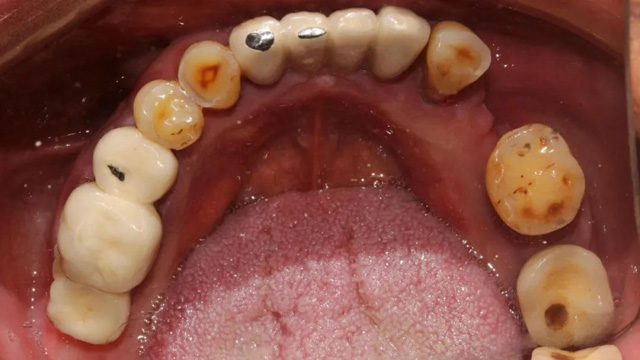

吳叔叔當時的口腔情況

“上面種了4顆,斷了兩顆,脫落1顆,只有1顆能用,下面有一顆牙冠脫落,另一顆有種植體周圍炎,有明顯的骨吸收。”吳叔叔剩下的天然牙也不好,做了幾處修復,之前的牙冠修復用的都是烤瓷牙,有好幾顆磨損嚴重露出了金屬。由于存在缺牙、不良修復體等情況,口腔整體咬合紊亂,進食很困難。